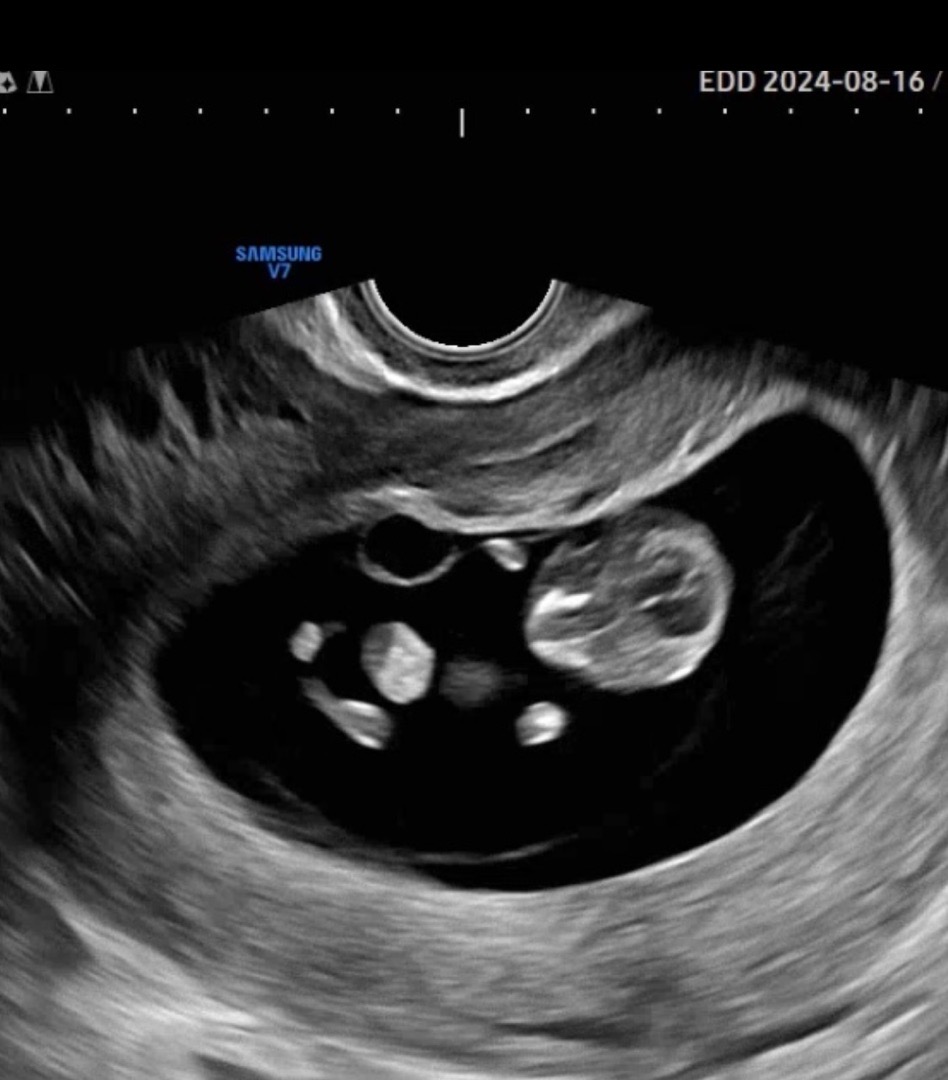

10주 1일차 촘파

10주가 되니 손발이 잘 보이고 꼬물꼬물 움직이는것도 보여서 너무 귀여워요 2주뒤 목투명대 검사하는데 벌써 긴장되네요 모든 산모님들 화이팅이에요!